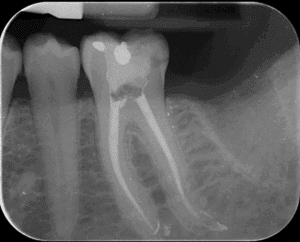

Figure 2 : Radiographie post-opératoire après traitement avec le Blue Shaper Pro (Zarc) et obturation avec le Neo Selaer Flo (Zarc by Avalon)